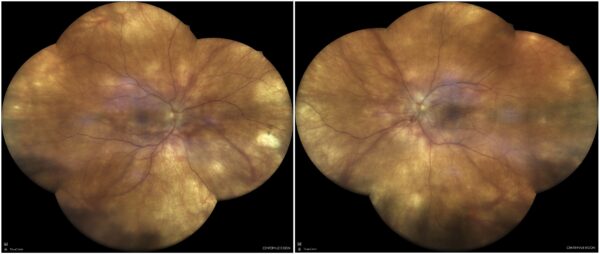

Figure 1: Fundus color photograph (iCare confocal high-resolution ultra-widefield Truecolor Centervue EIDON®) showing a hypopigmented fundus and optic disc edema in both eyes, along with mild vitritis. Deep, small, yellow nummular lesions can be noted in the mid periphery bilaterally (Dalén-Fuchs nodules).

A 44-year-old Caucasian woman was referred for multimodal fundus imaging as part of the propaedeutic evaluation of bilateral papilledema. Her symptoms had begun 9 months earlier and included transient vision loss, floaters, photophobia, headaches, and a “heavy head” sensation. She also reported some neck stiffness and tinnitus. Her past medical history was unremarkable except for alopecia and vitiligo. Her family history was negative for ophthalmic diseases. Upon examination, her corrected distance visual acuity (CDVA) was 6/10 bilaterally, with discrete against-the-rule astigmatism in both eyes (BE). The eyes were calm but biomicroscopy revealed subtle inferior keratic precipitates (KPs), cells in the anterior chamber (1+), and flare (1+). Intraocular pressure (IOP) was within the normal range bilaterally. Fundoscopy showed vitritis (1+), a hypopigmented fundus, blurred optic disc margins, and Dalén-Fuchs nodules in BE (Figure 1).